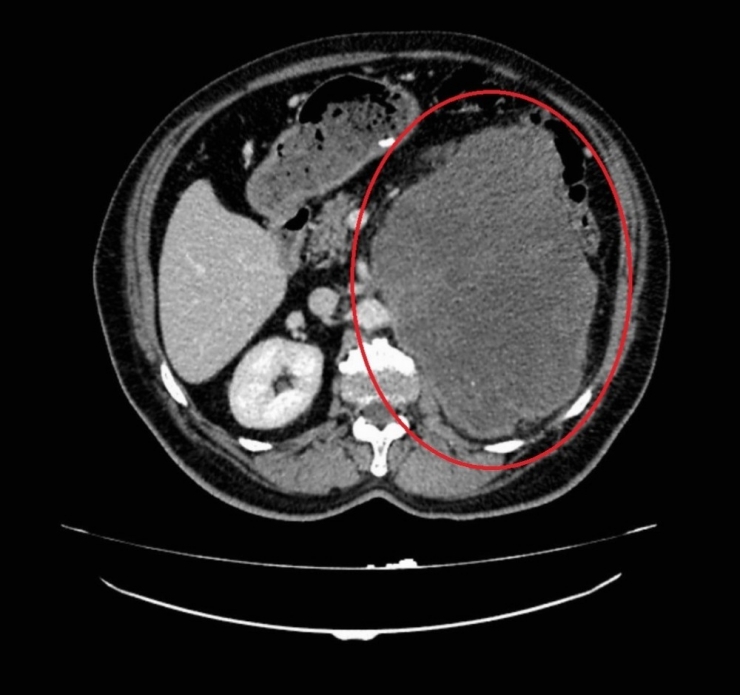

Samsun'da 62 yaşında erkek hasta sol yan ağrısı ve karın şişliği şikayetleri ile OMÜ Tıp Fakültesi Hastanesi Üroloji Kliniğine başvurdu. Hastanın yapılan muayene ve tetkikleri sonucunda böbreğinde 20 santim boyutunda tümör tespit edildi. Başarılı bir ameliyatla çıkarılan kitlenin patoloji sonucu miksofibrosarkom olarak saptandı. Normalde kol ve bacaktaki yumuşak dokulardan kaynaklanan bu tümör türünün böbrekte görülmesine oldukça şaşırdıklarını belirten OMÜ Tıp Fakültesi Üroloji Anabilim Dalı Öğretim Üyesi Doç. Dr. Berkan Reşorlu, olgularını 2015 yılında İspanya'da görülen vakanın ardından dünyada görülen ikinci vaka olarak ürolojinin prestijli dergilerinden birinde yayınlattıklarını belirtti.

Yapılan operasyon ve hasta hakkında bilgi veren Doç. Dr. Berkan Reşorlu, "Hastamız sol yan ağrısı ve karında şişlik şikayeti ile bize başvuran 62 yaşında bir erkekti. Yaptığımız muayene ve radyolojik görüntülemeler sonucunda sol böbrekten kaynaklanan 20 santim boyutunda bir kitle olduğunu tespit ettik. Bunun üzerine hastayı ameliyata alarak, başarılı bir operasyonla böbrekle birlikte kitleyi çıkardık. Çıkardığımız kitlenin patoloji sonucu sıklıkla kol ve bacaktaki yumuşak dokulardan kaynaklanan "miksofibrosarkom" dediğimiz kötü huylu bir tümör olarak geldi. Böyle bir tümörün böbrekten kaynaklanmasını beklemiyorduk. Literatürü araştırdığımızda böbrekten kaynaklanan tek "miksofibrosarkom" vakasının 2015 yılında İspanya'dan bildirildiğini gördük. Bunun üzerine bizde olgumuzu hızlı bir şekilde ürolojinin prestijli dergilerinden birinde yayınlattık ve dünyada görülen ikinci vaka olarak literatüre kazandırdık. Hastamızın kitlesi oldukça büyük, çevre organlara yapışık ve ana damarları tamamen sarmış durumdaydı. Oldukça riskli ve zor bir ameliyatın ardından bu kitleyi çıkartarak kemoterapi tedavisine başladık ve şu an hastamızı yakın takip altında tutuyoruz. Böbrek tümörleri, ürolojide prostat ve mesane kanserlerinin ardından en sık izlenen 3. kanser türü ve son yıllarda görülme sıklığı tüm dünyada artıyor. Tüm kanserlerde olduğu gibi bunlarda da erken tanı oldukça önemli. Ancak bu kanser türü sıklıkla tesadüfen saptanıyor. Çünkü hastaların ancak yüzde 10-15'lik kısmında idrardan kan gelmesi, karında şişlik ya da yan ağrısı gibi şikayetlere yol açıyor. Kendilerinde bu tip belirtiler izleyen hastaların vakit kaybetmeden bir üroloji uzmanına başvurmasını öneriyoruz" dedi.